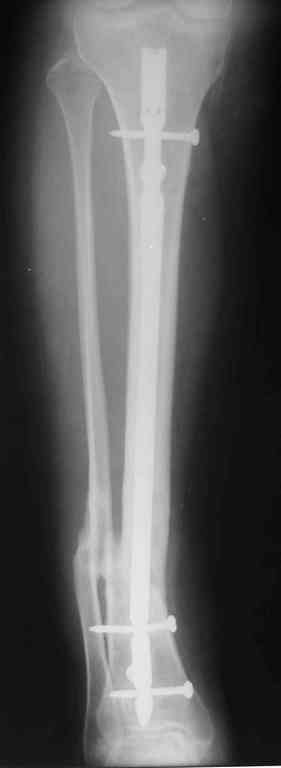

Re: Ложный сустав голени перелом штифта

Прилагаются.